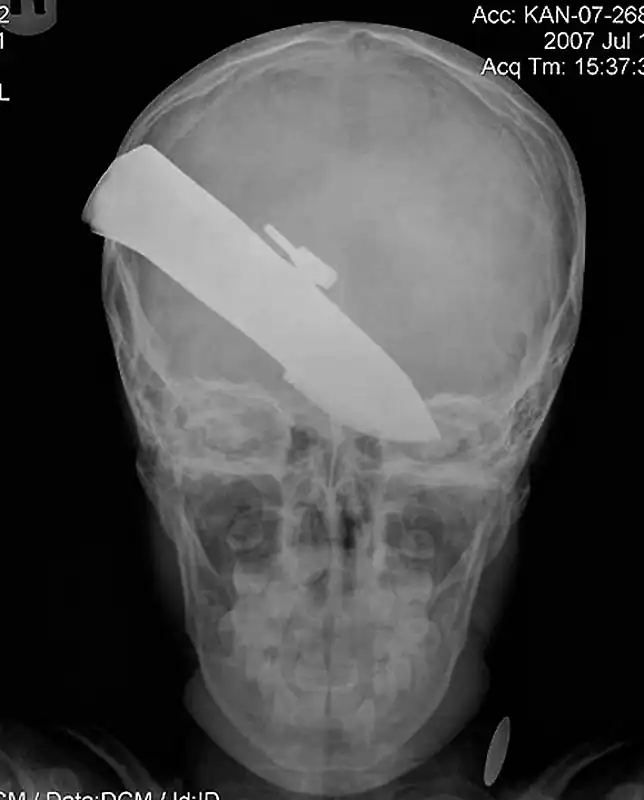

12-сантиметровый нож в черепе подростка.